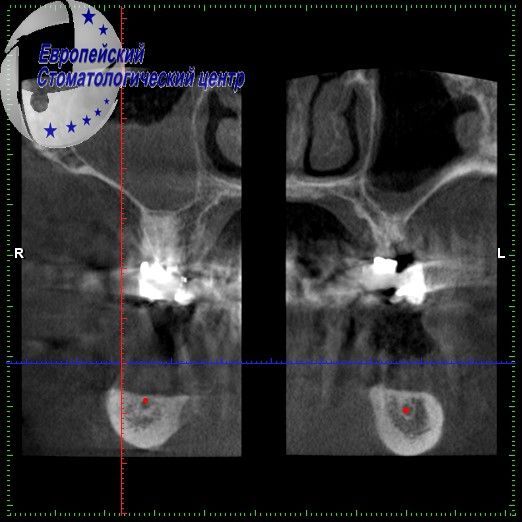

She had previously installed implants in another clinic, but disagreed with the treatment plan proposed there before prosthetics, she applied to our clinic. The proximity of the mandibular nerve significantly complicated the clinical situation for possible preimplantation (see pic. 3). An additional 4 implants were installed to bypass the mandibular nerve (see pic. 4-5).

Picture 3

Picture 4

Picture 5